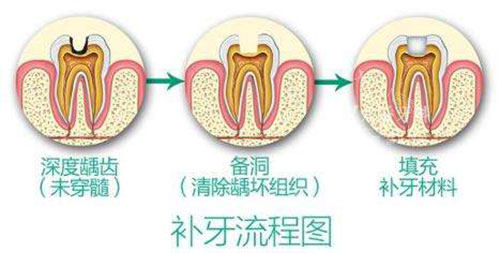

补牙拔牙价格

补牙:70 元起

拔普通牙:100 元起

拔智齿:160 元起

根管治疗:380 元起

牙周护理:230 元起